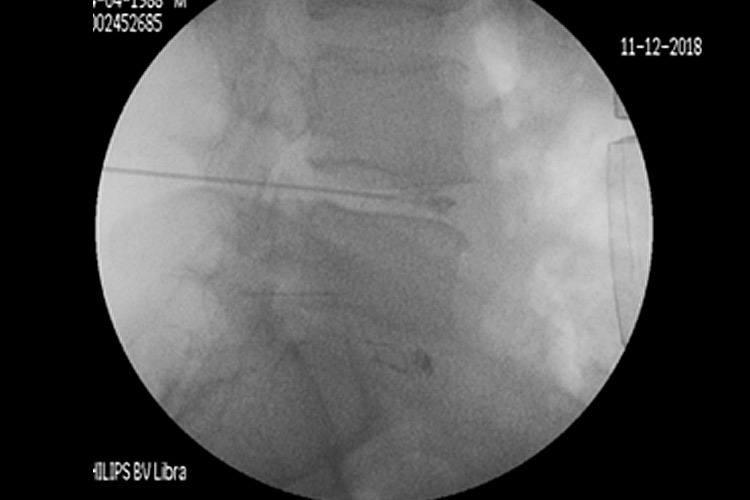

Χρησιμοποιώντας την εφαρμογή ραδιοσυχνοτήτων, εισάγεται, αρχικά, ένας οδηγός κάτω από ακτινοσκοπικό έλεγχο στον μεσοσπονδύλιο δίσκο και κατευθύνεται έμπροσθεν της κήλης. Μέσα από τον οδηγό εισάγεται ένα ηλεκτρόδιο, που η άκρη του έχει τη δυνατότητα κίνησης και στροφής 360ᵒ (Σχ. 1).

Περίπτωση 1: Ακτινοσκόπηση σε Διαδερμική Δισκοπλαστική με χρήση ηλεκτροδίου (RF) σε κήλη μεσοσπονδυλίου δίσκου Ο4-Ο5. |